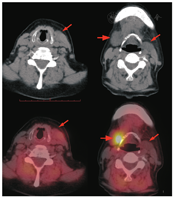

正常的甲状旁腺有2对,上甲状旁腺通常位于甲状腺上极后方或靠近环状软骨,下甲状旁腺多位于甲状腺下极后方或下方。本例甲状旁腺显像显示的可疑异常位置较靠上,而甲状腺区域未见异常,超声未提示该区域有甲状旁腺相关的异常,所以要考虑异位甲状旁腺的可能。为进一步明确定位诊断,患者行99Tcm-MIBI SPECT/CT显像(图3),可见左侧胸锁乳突肌内侧稍低密度结节,上缘达颌下水平(长箭头示),与超声所见部位一致,但放射性摄取未见增高;右侧颌下结节摄取明显增高(短箭头示)。右侧的颌下结节从形态、99Tcm-MIBI摄取情况来看都可以看作是颌下腺的表现,但其位置较正常颌下腺略偏低(下缘达到甲状软骨上缘),且左侧颌下腺未见显示,理应不是正常颌下腺的表现。考虑到甲状旁腺位置变异时可位于颈动脉分叉至心包的任何部位,本例的2处可疑病变均需鉴别异位甲状旁腺发生的腺瘤或增生:右侧颌下区结节的99Tcm-MIBI摄取支持甲状旁腺腺瘤或增生,但需与颌下腺鉴别(如某些原因导致的仅单侧颌下腺显示的可能性);左侧胸锁乳突肌内侧结节在99Tcm-MIBI早期显像可见轻度摄取,但2 h延迟显像时其摄取较前减低,SPECT/CT显像呈阴性表现,并不是甲状旁腺腺瘤或增生的典型表现。